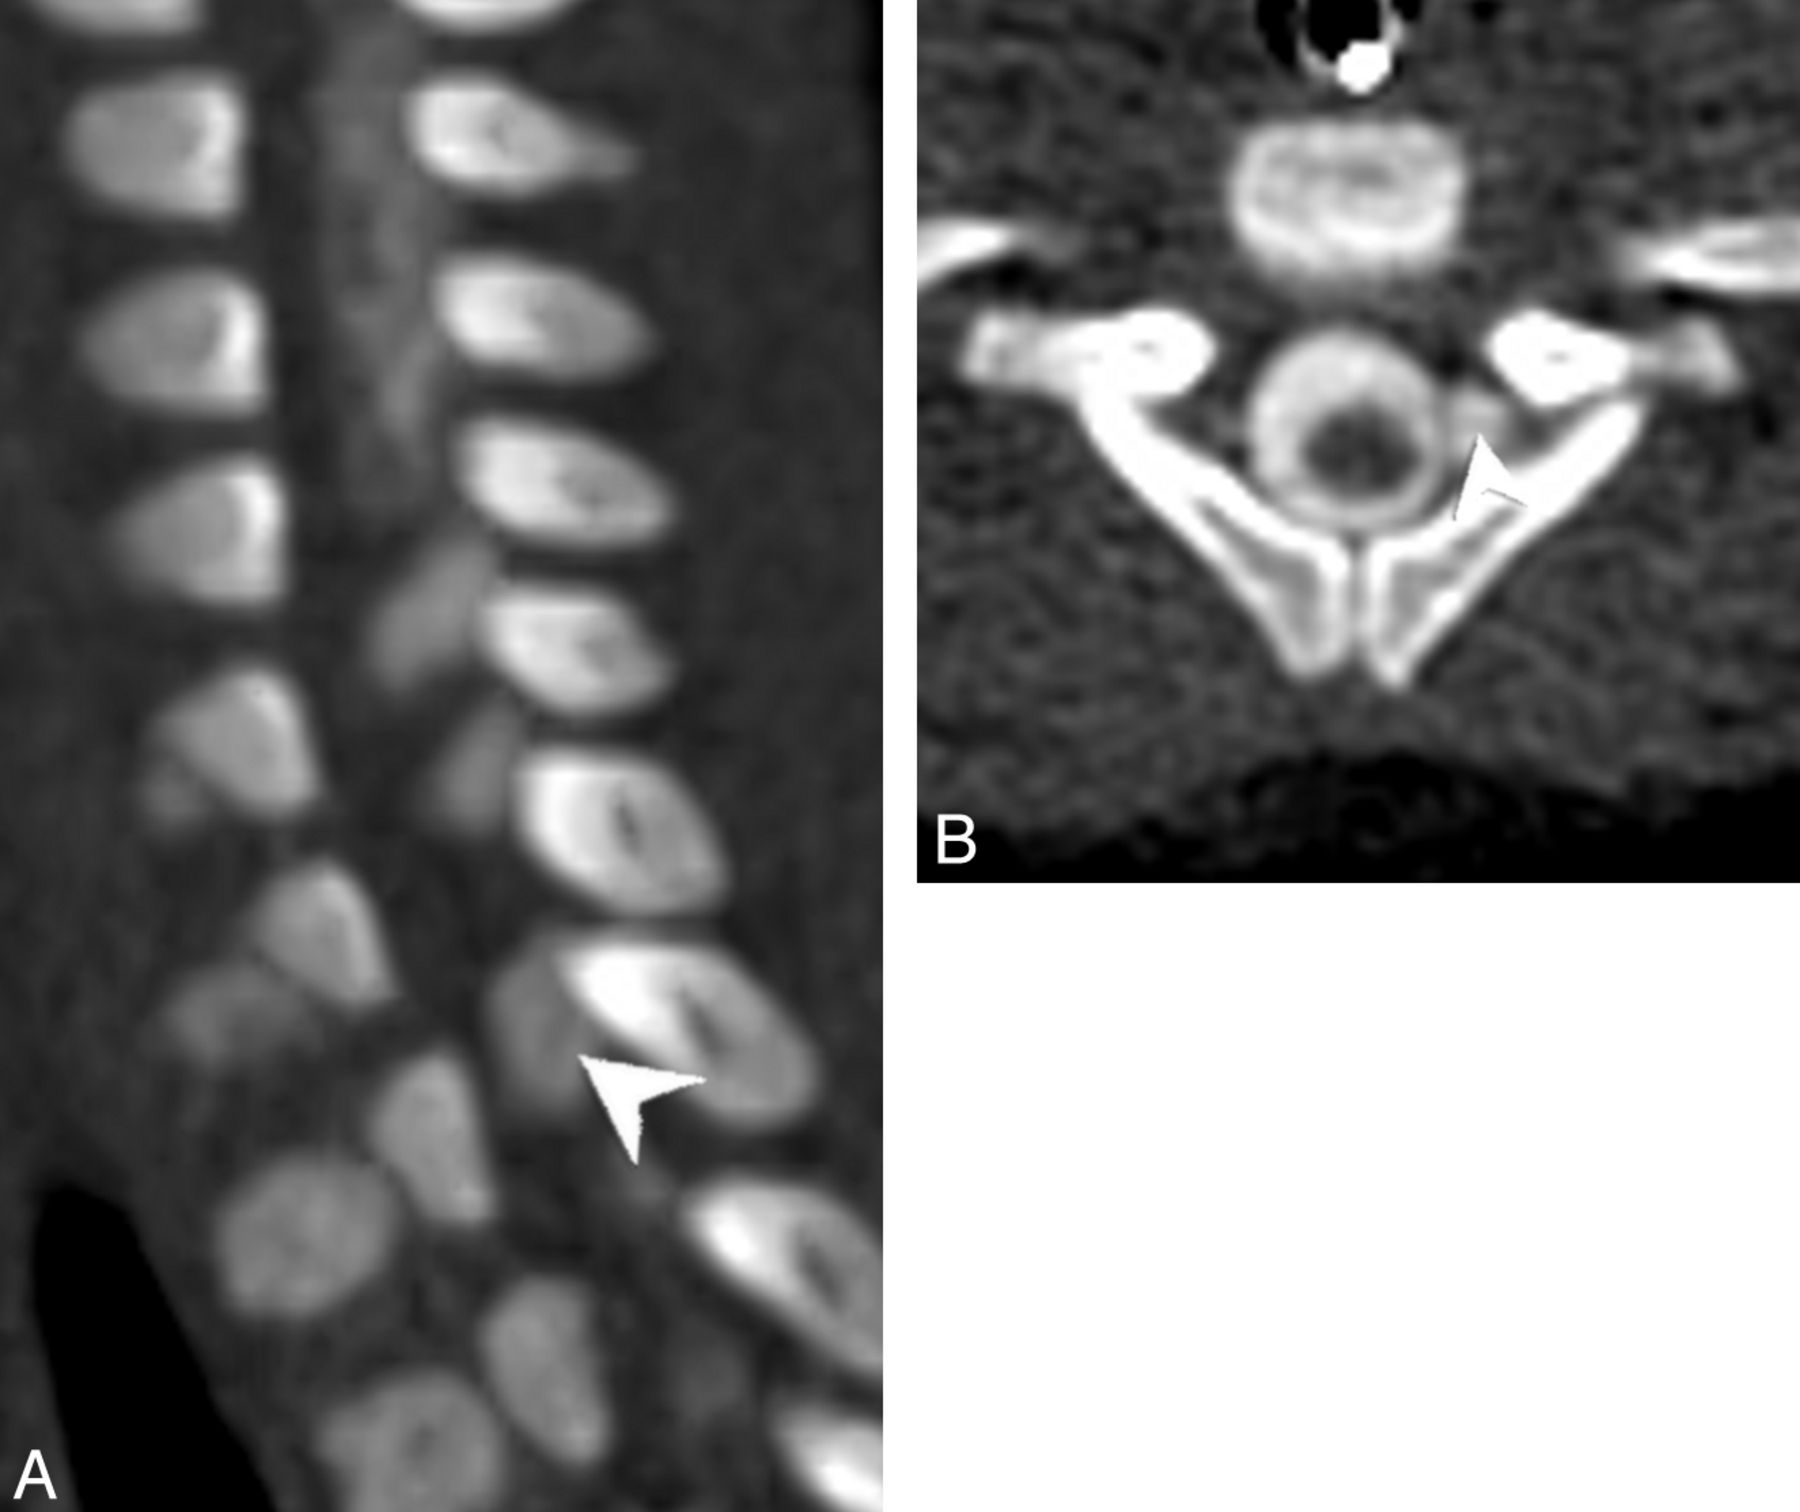

Left parasagittal (A) and axial (B) images from a CT myelogram demonstrating a left-sided pseudomeningocele at T1. A thin linear filling defect within the pseudomeningocele continued centrally to the cord and was interpreted as an intact nerve root.